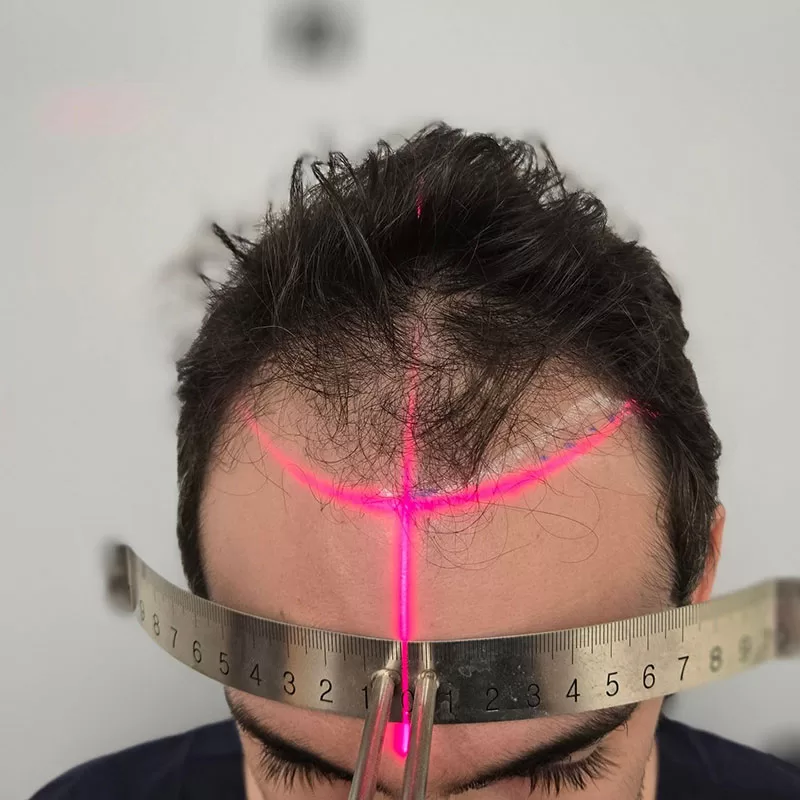

Η ελάχιστη επεμβατική τεχνική Μεταμόσχευσης Μαλλιών FUE είναι μια σύγχρονη μέθοδος όπου εξάγονται τα τριχοθυλάκια μεμονωμένα (ένα προς ένα) απευθείας από τη δότρια περιοχή του ασθενή και στην συνέχεια μεταμοσχεύονται στην λήπτρια περιοχή με τη χρήση ενός ειδικού εργαλείου εμφύτευσης (Implanter Pen/ Choi Pen/ DHI), στη σωστή κατεύθυνση και γωνία της τρίχας προσφέροντας στον ασθενή φυσικό και μόνιμο αποτέλεσμα με ελάχιστο χρόνο επούλωσης – αποθεραπείας και χωρίς τα μειονεκτήματα των μεγάλων ορατών ουλών σε σχέση με παλαιότερες μεθόδους.

ΧΩΡΙΣ ΓΡΑΜΜΙΚΗ ΟΥΛΗ – ΧΩΡΙΣ ΡΑΜΜΑΤΑ

Το πρωτόκολλο που εφαρμόζουμε ελαχιστοποιεί τον χρόνο που τα τριχοθυλάκια παραμένουν εκτός σώματος, ενισχύοντας τα ποσοστά επιβίωσης των μοσχευμάτων και έτσι διασφαλίζετε η καλή πυκνότητα του αποτελέσματος. O Δρ. Κωνσταντίνος Διονυσίου, για την εξαγωγή χρησιμοποιεί τελευταίας γενιάς εργαλεία Cole Instruments (USA) και Trivellini (Paraguay) τα οποία θεωρούνται απο τα πιο σύγχρονα στον κόσμο, αυτή τη στιγμή.

Η τεχνική μεταμόσχευσης μαλλιών FUE, σε αντίθεση με άλλες τεχνικές, επιτυγχάνει πάνω από 95% βιωσιμότητα των μοσχευμάτων και διατήρηση των εμφυτευμένων τριχών σε Α – Β Ζώνη. Σε μία μόνο επίσκεψη, μπορούμε να μεταμοσχεύσουμε πάνω από 2500 μοσχεύματα (περίπου 6500 τρίχες), πετυχαίνοντας τη μέγιστη δυνατή πυκνότητα.